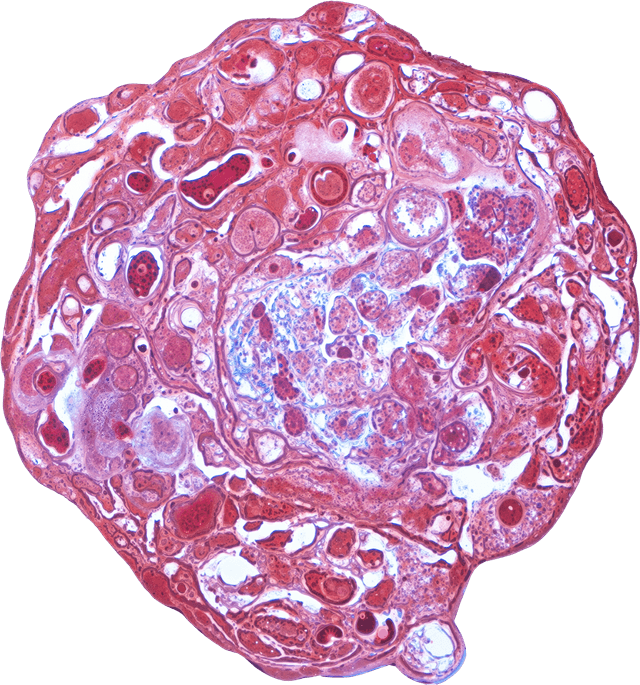

VitroScreen, a SenzaGen Group company, pioneers next-generation in vitro testing solutions. We leverage cutting-edge biological models—from 2D cells and reconstructed tissues to ex vivo systems and cellular spheroids—to deliver precise, human-relevant data for the Cosmetics, Medical devices, Nutraceuticals, Pharma and Chemicals industries.

Our models mirror human biology for precise, predictive accuracy.

We design and execute rigorous preclinical in vitro studies, combining validated testing standards with fully customized protocols to deliver reproducible, decision-ready results. Our expertise covers multiple product categories and therapeutic areas, providing highly predictive platforms for both regulatory and efficacy assessment.